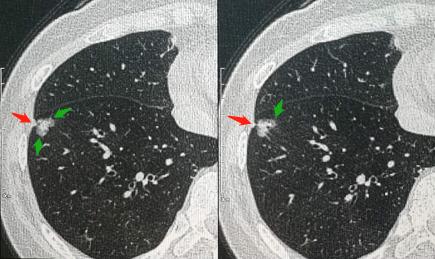

第一位是56岁的女士,咳嗽20多天,吃药不管用,主动要求做胸部CT检查:

在右下肺靠近边缘区,查出一个混合磨玻璃密度结节,伴有胸膜牵拉(红箭头),病灶边缘可见清晰的磨玻璃密度影(绿箭头),直径1.3cm。

1.边界清晰的混合磨玻璃密度结节,伴有胸膜牵拉,提示肺腺癌;

2.小于2厘米的早期肺癌,很少含有分化不良的成分。

所以这是一例早期肺腺癌,预后良好,手术切除可以治愈!

而且这个病灶位于肺边缘胸膜下,不需要开胸手术,采用胸腔镜下微创切除即可。